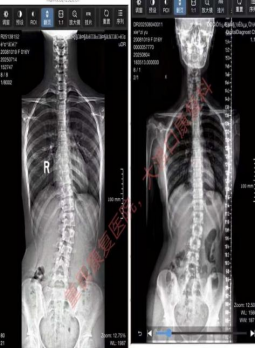

往期训练营已帮助众多青少年成功改善脊柱侧弯问题,通过治疗前后的专业对比,清晰呈现弯曲角度矫正、体态改善的显著效果,用实力护航脊柱健康。